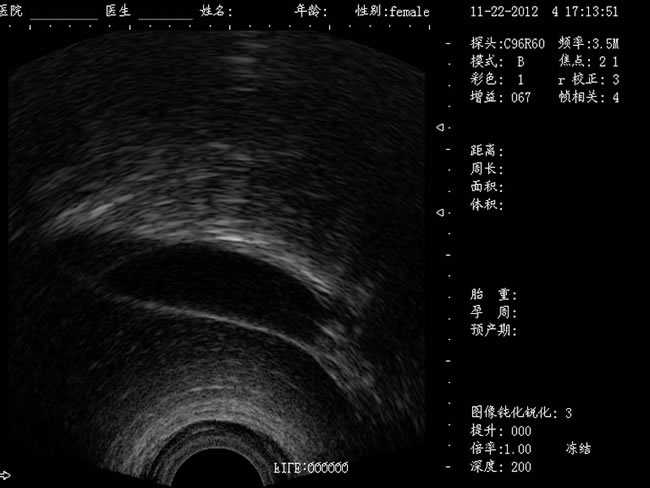

DW-400

功能特點:

定位精確 手術效率高:實時動態頻率掃描等全數字超聲成像技術、生成精確的圖像引導手術器械迅速到大手術位置,避免損傷子宮內膜和子宮穿孔的現象,即減輕了患者的痛苦又極大提高了手術效率。

高密度全數字波束形成:采用全新一代混頻技術、數字嵌入系統及數字整序技術

有效提升系統的穩定性、可靠性:實時動態孔徑成像,充分保證圖像的精度和清晰度

標準配置:

主機

CXA10R/6.5MHz 腔內探頭

12.1英寸LED液晶顯示器

擴陰器

選配:CXA60R/3.5MHz 凸陣探頭

隨著醫療技術水平的提高,目前婦產科手術中所應用的相關設備也有了加大的改進。尤其是在人工流產手術中,將B超婦產科手術監視儀應用到手術過程中,彌補傳統手術中所采用設備的不足之處,減輕手術中患者的疼痛感覺,使得手術順利的完成。這種儀器相比于傳統的儀器來說,其在操作上更為方便和簡單,能夠對妊娠反應有很好的療效。